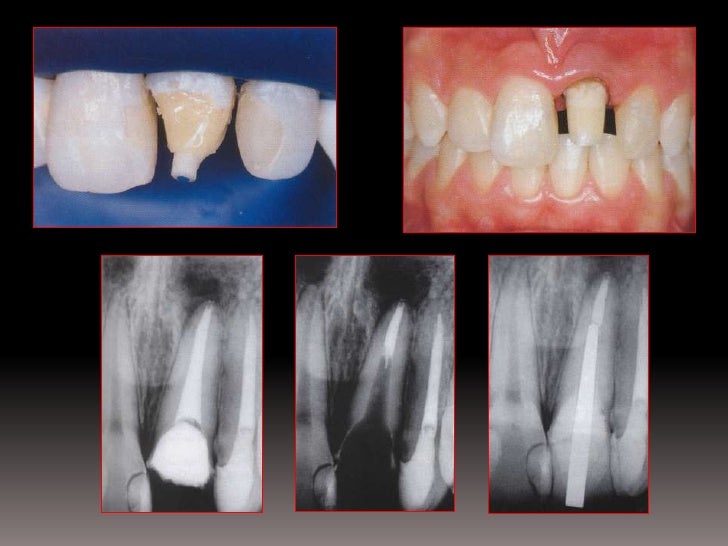

Pernos Intrarradiculares De Fibra De Vidrio Caso Clinico

www.actaodontologica.com